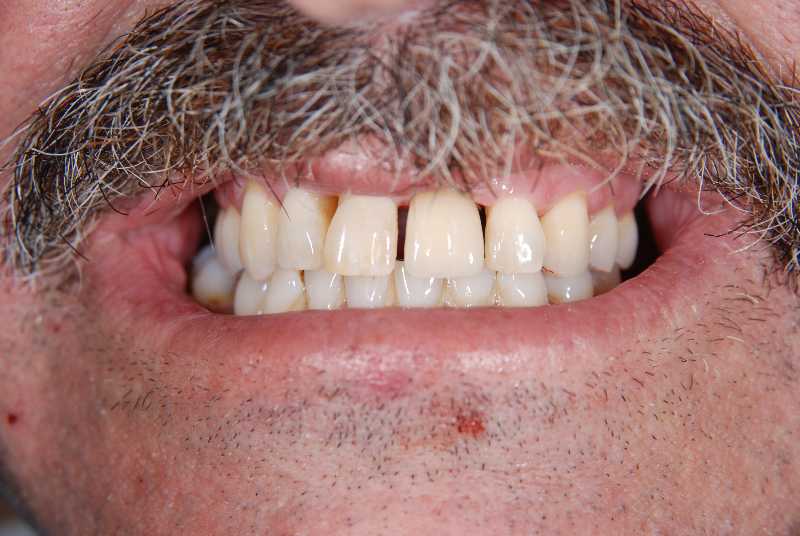

Intra oral view before placing the implants